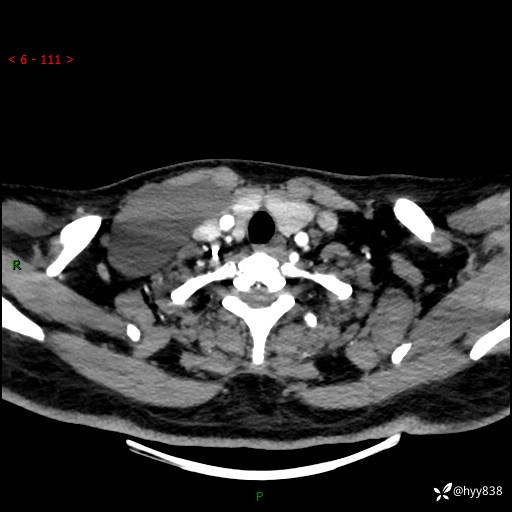

增强动脉期+静脉期